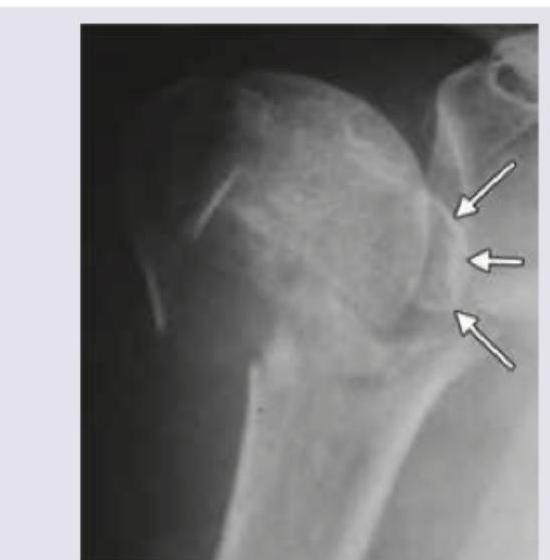

Question 1: What type of fracture is shown in X-ray of left shoulder?

- A. Neer classification grade 4

- B. Ideberg classification grade 4 (Correct Answer)

- C. Garden classification grade 3

- D. Schatzker classification grade 5

Explanation: ***Ideberg classification grade 4*** - The X-ray shows a **scapular fracture**, specifically involving the glenoid. Ideberg classification is used for **glenoid fractures**. - An Ideberg grade 4 fracture involves a **transverse fracture below the scapular notch**, separating the load-bearing part of the glenoid from the rest of the scapula, which appears consistent with the image. *Neer classification grade 4* - The **Neer classification** system is used for **proximal humerus fractures**, not scapular fractures. - A grade 4 Neer fracture involves **four part displacement** of the humeral head, greater tuberosity, lesser tuberosity, and humeral shaft. *Garden classification grade 3* - The **Garden classification** system is specifically used for **femoral neck fractures**, which are fractures of the hip. - A Garden grade 3 fracture represents a **complete, displaced fracture of the femoral neck**, distinct from the shoulder injury shown. *Schatzker classification grade 5* - The **Schatzker classification** system is used for **tibial plateau fractures**, which are fractures of the knee joint. - A Schatzker grade 5 fracture involves a **bicondylar fracture** of the tibial plateau, which is severe and impacts the knee, not the shoulder.